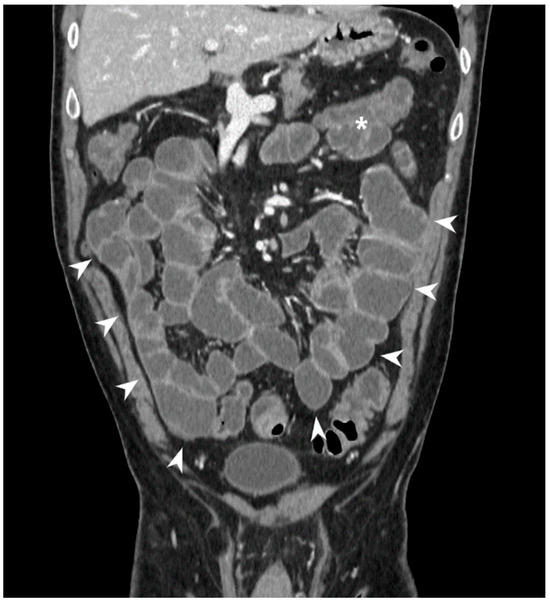

7. How Does Imaging Help Defining Disease Extension and Localization?